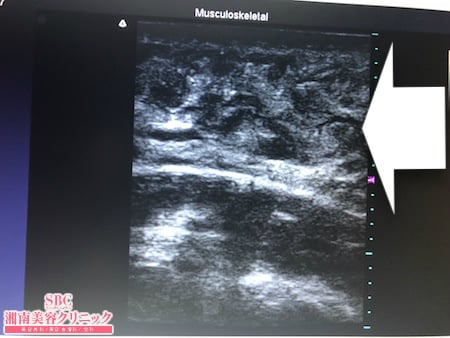

No.229115【脂肪吸引】【動画あり】湘南美容外科脂肪吸引最高責任者である竹田先生による脂肪吸引のフォトギャラリー!太ももの脂肪吸引に大満足して今度は二の腕を細くする!術中3Dタッチビュー・左二の腕